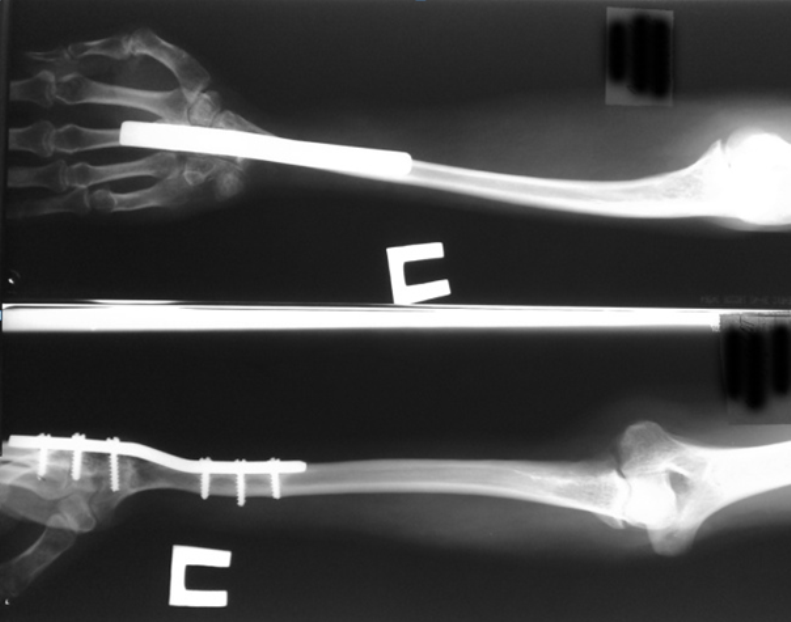

Радиоульнарный угол: строение и особенности лучевой кости